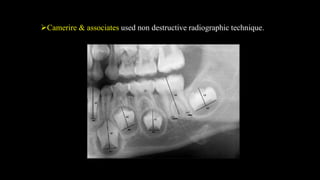

Camerire & associates used non destructive radiographic technique.

Camerire & associatesused non destructive radiographic technique.